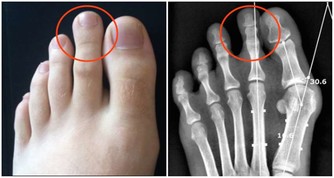

1、關節腫痛

日常生活中,很多人都會出現關節腫痛的問題,高尿酸就是其中的一個原因,如果體內的尿酸過高,就會有大量尿酸結晶,而這些結晶很難排出,只會留在我們的關節中。時間久了,就會出現關節疼痛的現象,這時建議及時去醫院檢查,查明原因,及時調理。